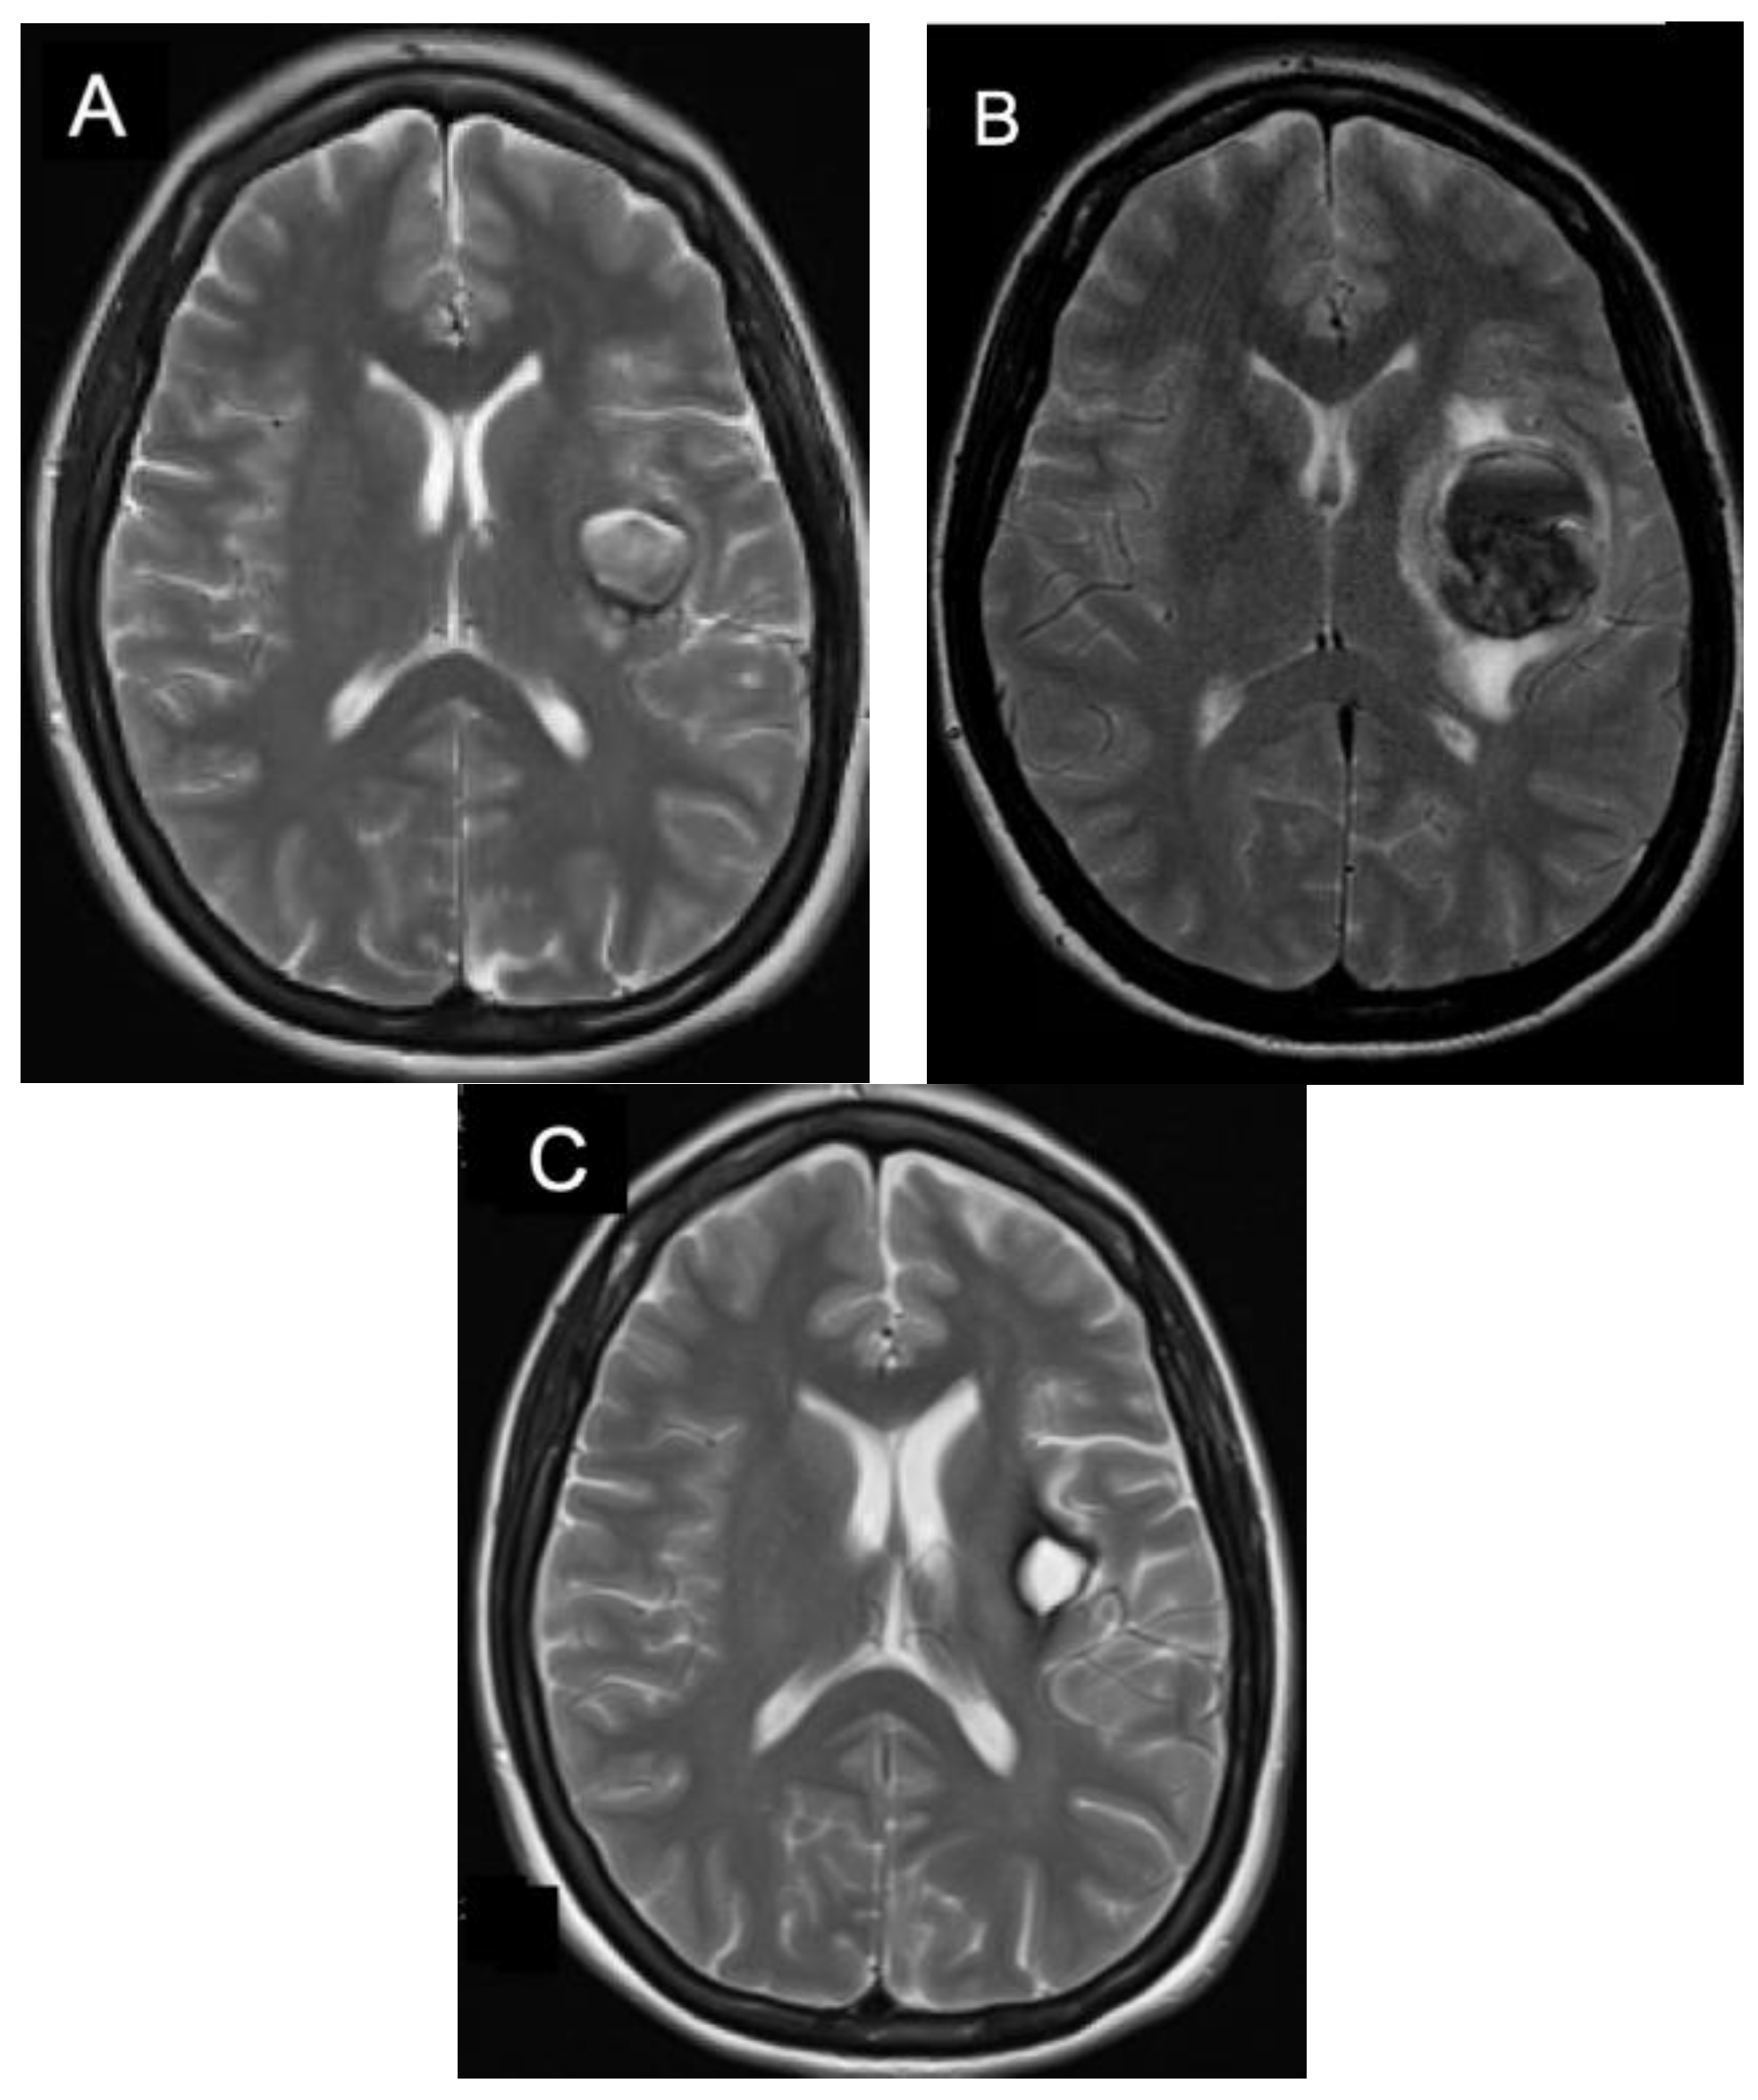

5. Management of Incidental Cavernomas

6. Management of Symptomatic Supratentorial Cavernomas

7. Management of Symptomatic Infratentorial Cavernomas